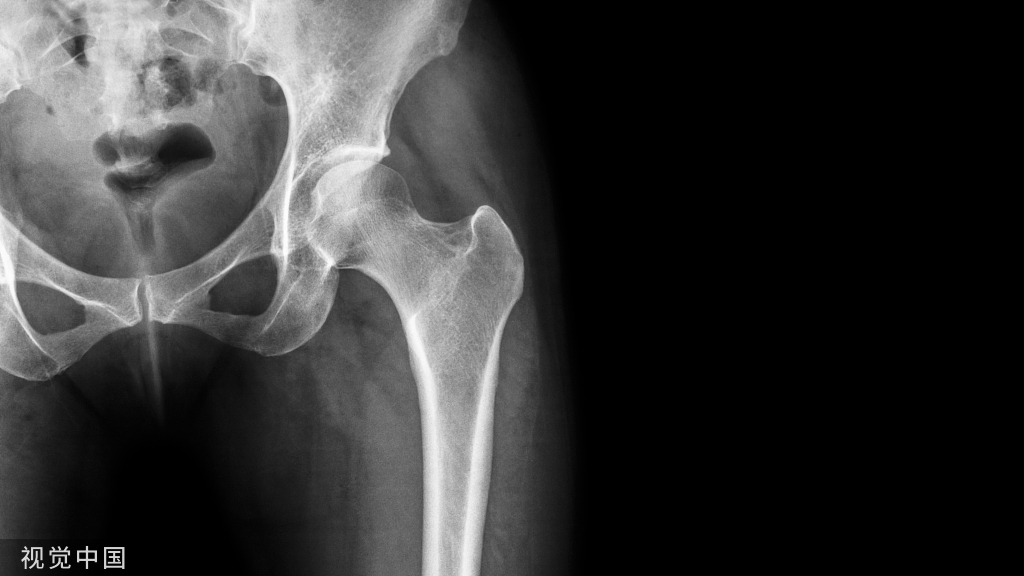

随着现代医学技术的发展,骨科手术越做越多、方法也越来越多,但石膏固定作为骨科医生的看家本领,不但不能忘,还要掌握精准。

石膏绷带固定指征

1、上肢、小腿以下部位的骨折整复后固定

2、某些骨折内固定术后,辅助治疗3、畸形校正后维持位置,如拇外翻4、骨与关节炎症的局部制动(结核)5、关节损伤和关节脱位复位后固定6、周围神经、血管、肌腱断裂或损伤,手术修复后的制动。

常见几种石膏固定术:

石膏固定的范围和时间: